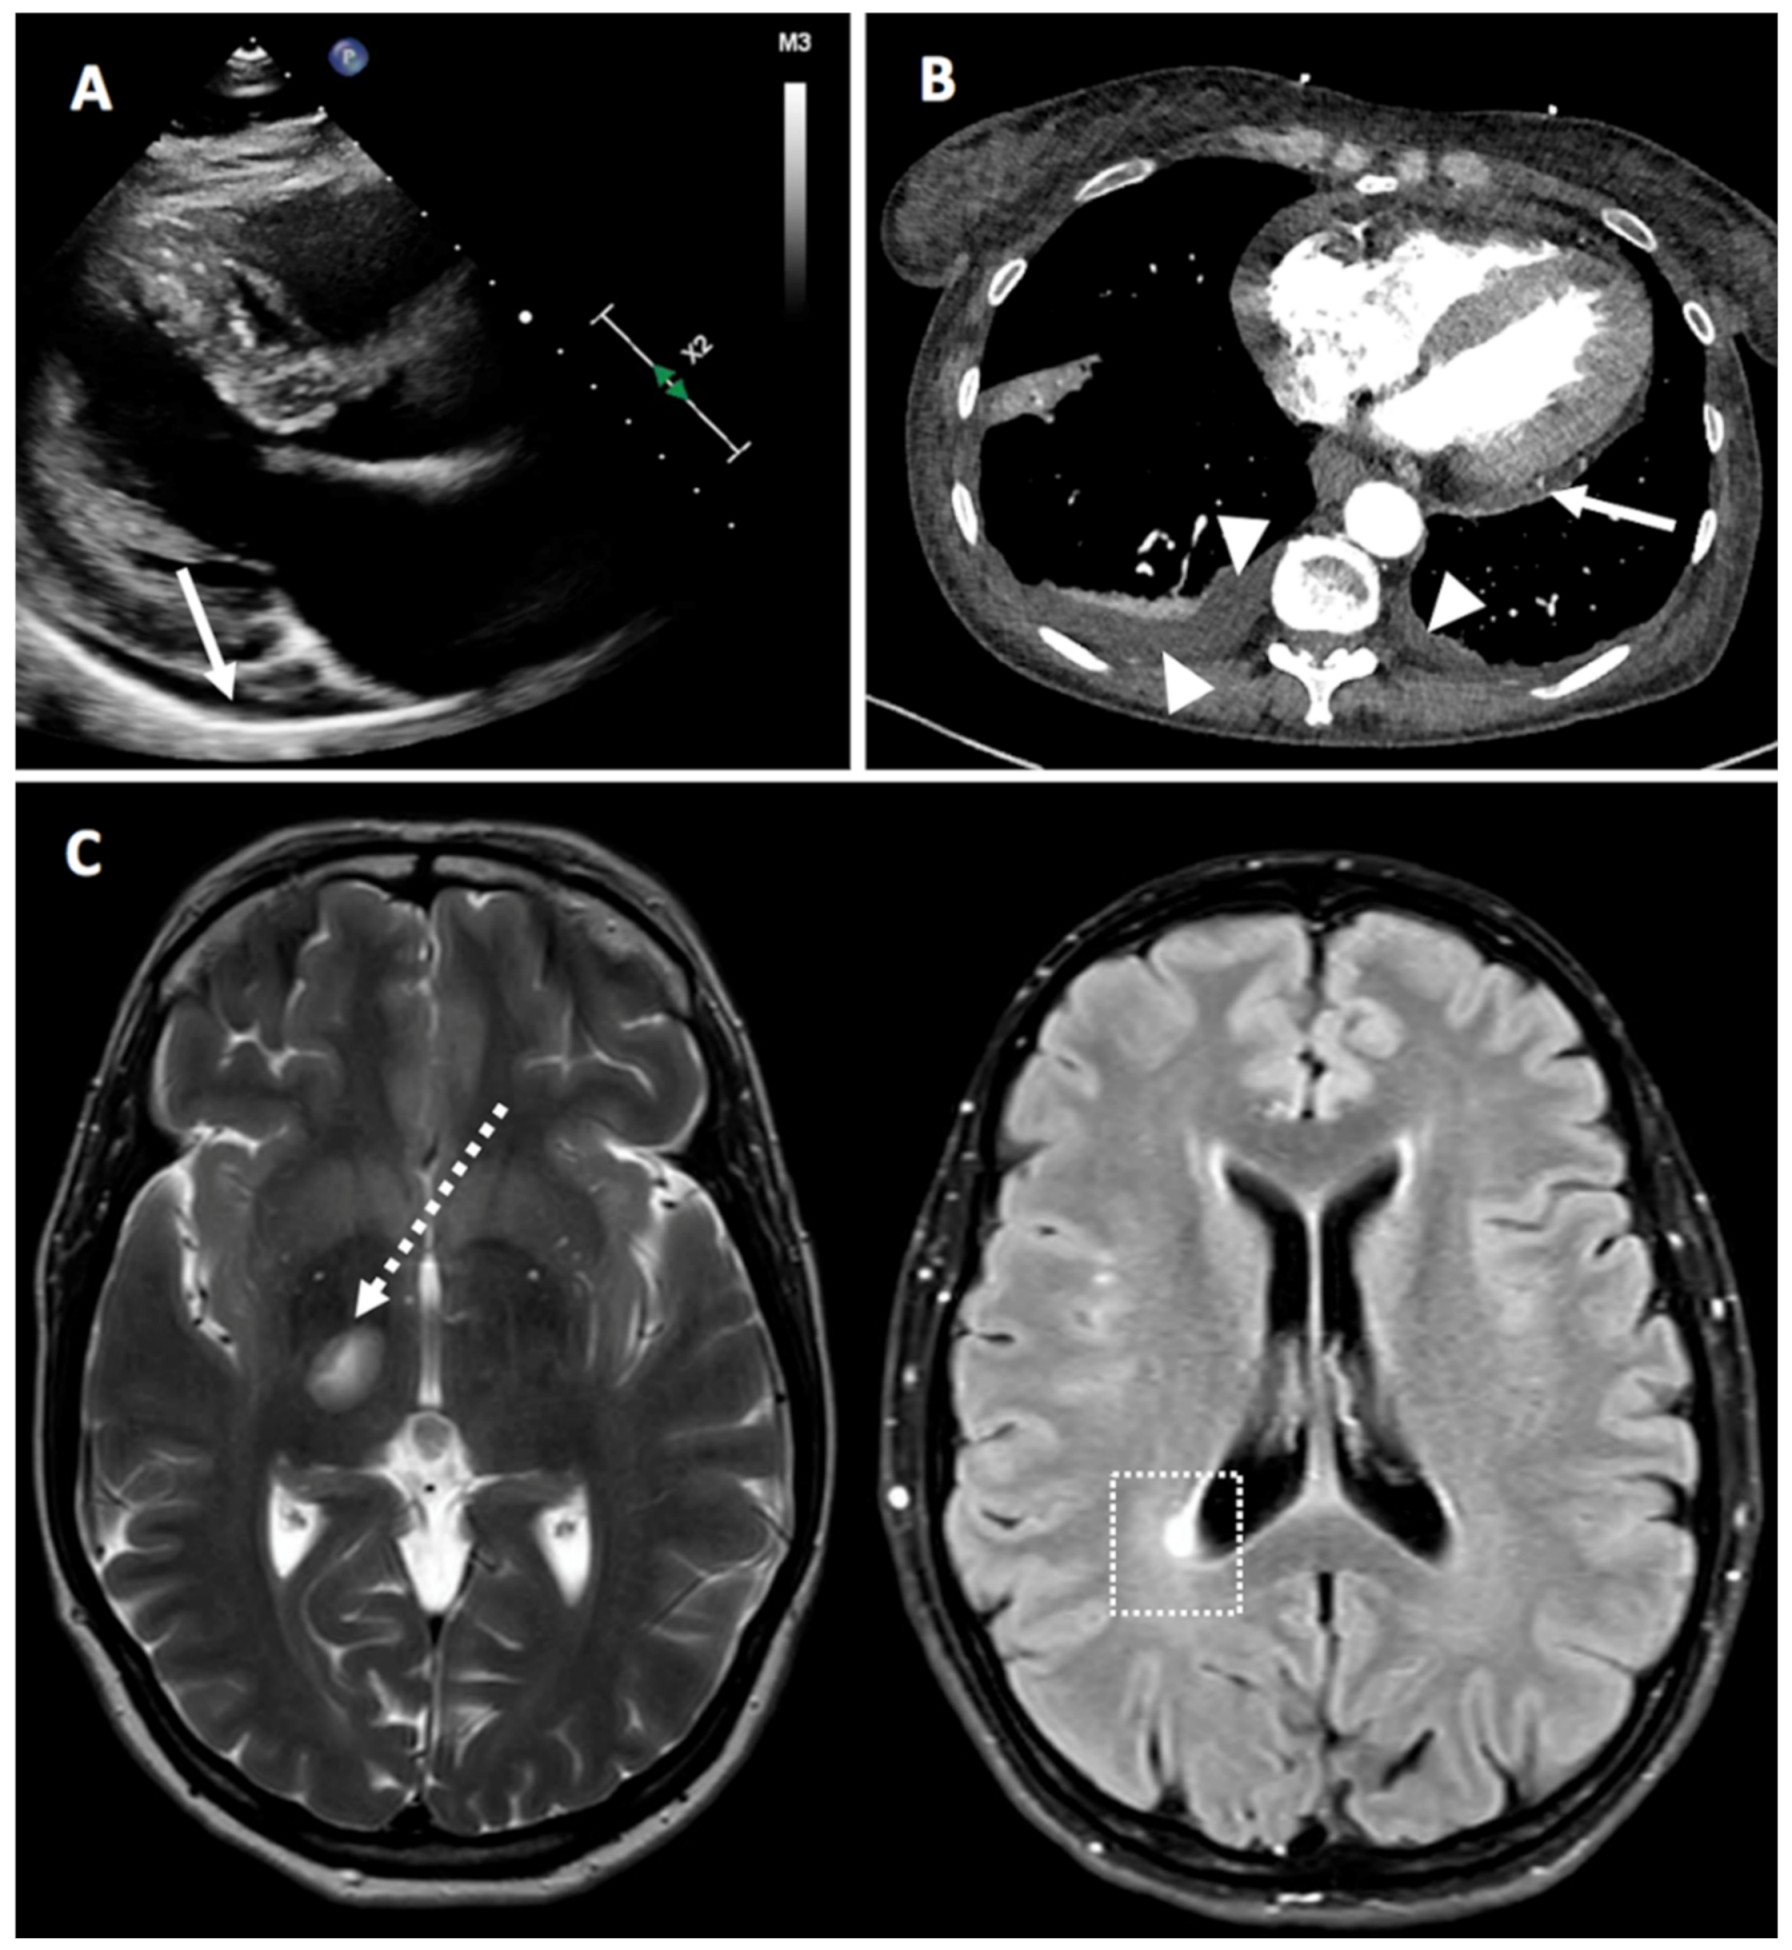

| 8 | F | 66 | Idiopathic pericarditis, anemia normocytic normochromic, left femoro-popliteal DVT treated with rivaroxaban 20 mg 12.2020, spontaneous abortion of 1st trimester Idiopathic pericarditis |

January 2021 BNT162b2 vaccine | Not given | 2 days after the 1st dose | Pericarditis with fever, typical pleuritic chest pain, elevated inflammation markers No RA articular manifestation. | F | Mild (moderate chest pain, no symptoms of heart failure, no limitation of function) | Positive ACPA 5.4, RF 44, CRP 40, ESR 70 | Continued Prednisone 15 mg prednisone. On 19 January 2021, dose was increased to 30 mg and 1 mg of colchicine. by physician. 15 mg of Methotrexate was started together with 5 mg of folic acid | Rapid response to therapy with quick symptom improvement. | Israel | No | No | Yes |

| 27 | F | 60 | SLE (never previously referred to rheumatology): Discoid lupus since 2001, severe raynauds, alopecia, pancytopenia (since September 2020), proteinuria (Developed Sept 2020, diagnosed as class IV lupus nephritis March 2021), hypocomplementaemia, ANA positive, dsDNA, anti-chromatin and anti-ribosomal antibody positive), 2019 EULAR/ACR SLE criteria) Baseline Disease modifying therapy: Prednisolone 8mg OD | February 2021 ChAdOx1 vaccine | Not given yet | 4 days | Pericardial and pleural effusions, possible pericarditis | F | Mild | Central intermittent pleuritic chest pain, had CTPA and bedside echo. Trop normal CRP 17.8 | Prednisone increased from 8mg to 15mg for 5 days, colchicine 500 mcg BD | Rapid response to therapy with quick symptom improvement | UK | Yes | Yes | Yes |